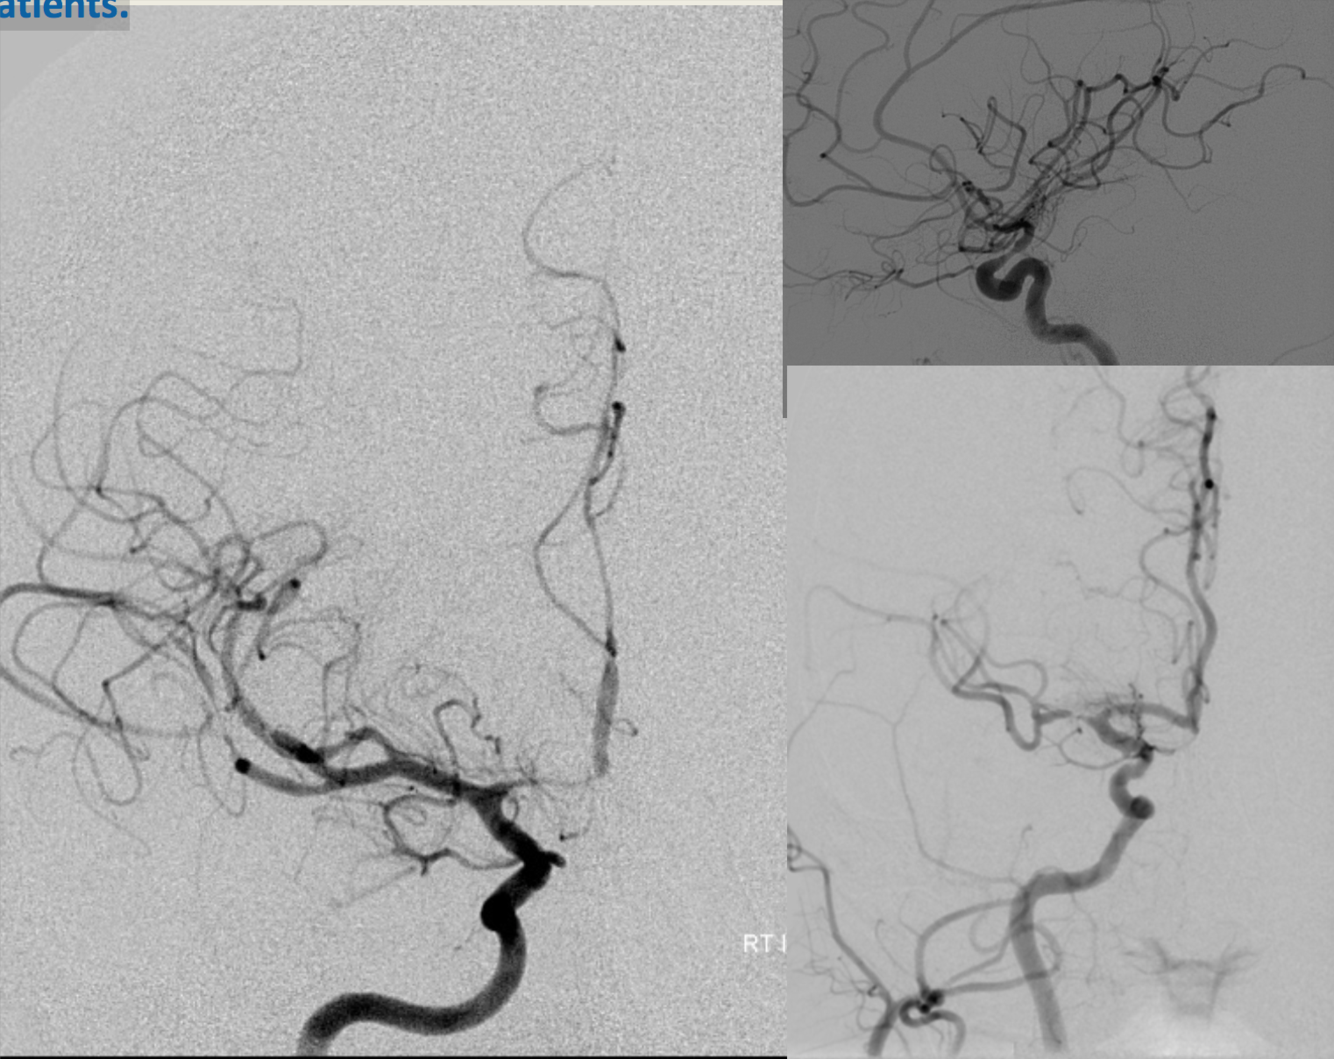

Angiograms after subarachnoid hemorrhage in different patients.

Vasospasm